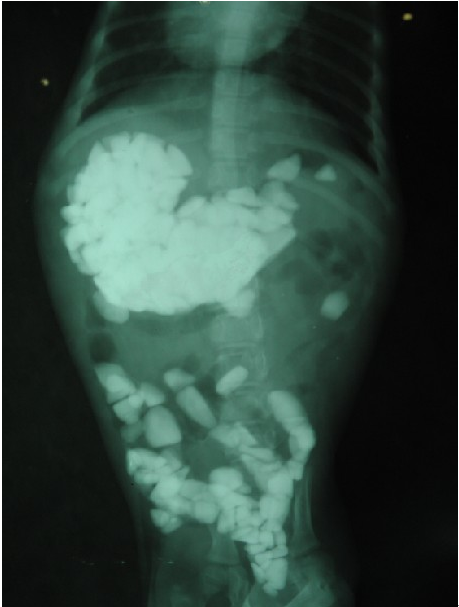

于是闹闹在BBMM,叔叔阿姨的陪同下来到名望宠物医院,MM把病情给医生叙述了一下,医生叔叔说:闹闹的好奇心很重,可能把石头吃进去了,我们先照个X线看看吧。这不照不知道,一照吓一跳啊!!

哇,这一肚子石头!!闹闹你也太牛了吧!!难怪突然长了几斤?!!

似乎也知道错了。医生叔叔说:闹闹这家伙也太调皮了,你们先不要着急,闹闹虽说吃了这么多石头,好在这些石头都不大。我先给他吃一些肠道润滑剂,回去后多在外面走走,今天就不要给他吃东西了,估计是可以排出来的。明天上午再来拍个片,如果没出来可能就要手术处理了;闹闹你可要加油哦!

第二天一早,医院才刚刚开门。闹闹就来医院了,BBMM兴奋地说:闹闹昨天很努力排了好大的几堆石头,今天明显感觉整个人轻松多了。于是又拍了片和昨天的做了对比。

哎!闹闹真是肉做的身体,铁打的肠胃啊!!真让人不敢相信!狗狗真是能创造奇迹啊!不过这种奇迹还是少一点比较好。